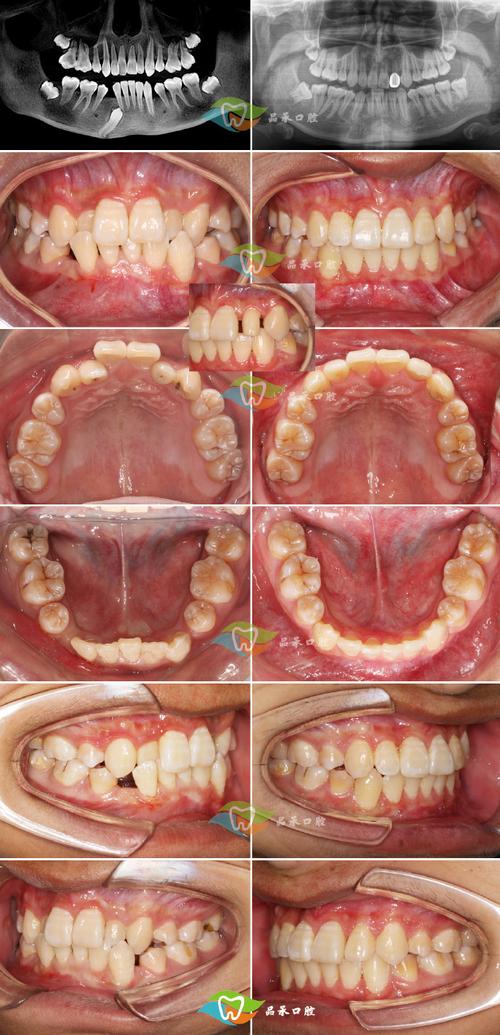

- 查看案例:要求医生展示Insignia真实案例(尤其类似您牙齿情况的)。